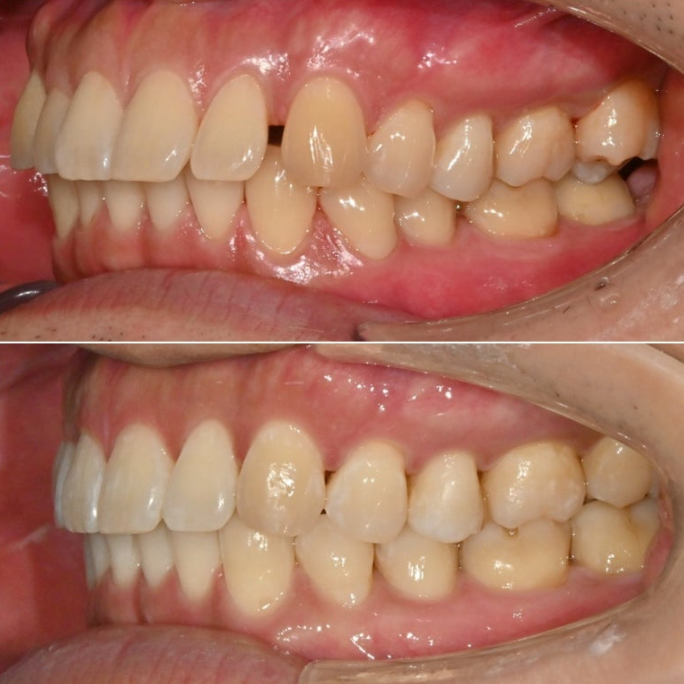

중심선은 처음에 비해 많이 맞아졌고 여전히 약간의 불일치가 남아있습니다.

아래 작은어금니의 완벽한 회전을 위해서 고무를 걸 부가장치를 붙인채 치료를 진행했습니다.

가위교합의 빠른 해결을 위한 입천장의 교정용 나사도 썼습니다.

안으로 쓰러져 있던 큰어금니도 잘 세워졌고 가위교합도 해소가 되었습니다.

또 고무줄의 힘으로 아래 작은어금니 회정는 1차세트에서 대부분 개선이 됩니다.

중심선 일치, 미세공간 등 추가개선을 위해 추가장치 제작에 들어갑니다.

25년 5월부터 10월까지 추가장치를 모두 낀 후 치료를 마무리

25.10

어금니 교합은 물샐틈 없는 1급 교합관계를 보입니다.